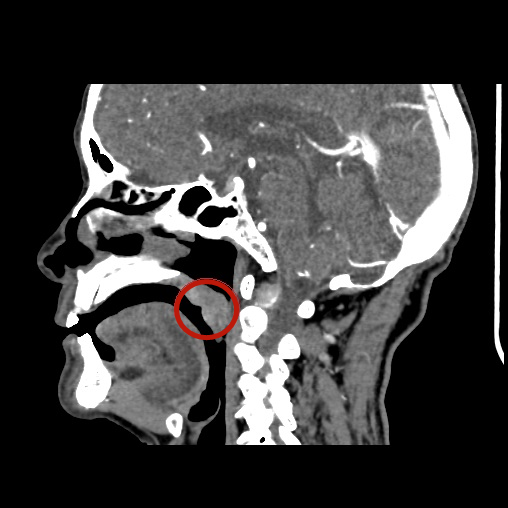

经过影像学检查,王爷爷腭部的肿瘤范围明确初步诊断为:软腭恶性肿瘤(鳞癌)

刘蓉蓉主任介绍道:「我们发现肿瘤侵犯了软腭全层,为了防止肿瘤复发,需要做扩大范围的切除。由于切除范围比较大,切除以后的创面修补会比较困难。幸运的是,目前肿瘤还局限在软腭范围内,没有侵犯硬腭,颈部淋巴结也没有发现有转移迹象。」

术中发现如刘主任术前评估的一致,王爷爷的软腭肿瘤不但侵犯了全层,而且范围比较大。肿瘤切除后,形成了直径约 2 cm 的腭部穿孔,加之口腔内操作空间极其狭窄,修补起来困难很大。刘主任运用扎实精湛的外科技术,对腭部穿孔进行了修补。